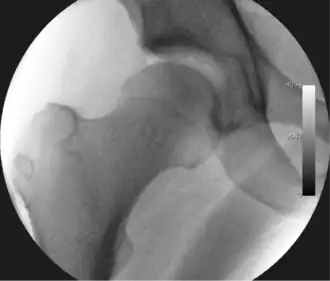

Figure 3. Fluoroscopic picture showing a mild amount of distraction of the hip before insertion of any instruments -

Figure 4. A needle is passed into the joint, breaking the 'suction seal', and allowing further distraction of the hip joint with minimal extra traction -

The procedure is performed with the patient asleep (general anaesthetic) or under spinal anaesthesia. There are two widely used methods, one with the patient on their back (supine) and the other on their side (lateral decubitus). Which is used is down to the surgeon's preference. To gain access to the central compartment of the hip joint (between the ball and socket), traction is applied to the affected leg after placing the foot into a special boot. (See fig. 2) There is specifically designed equipment for this, although some surgeons use a 'traction table', initially designed to help in the operative fixation of broken thigh and lower leg bones. The amount of traction (or pull) needed is assessed with the help of fluoroscopy (low-dose portable x-ray). (See fig. 3) It is usually not possible to distract the ball from the socket with traction alone by more than a few millimetres. Once the surgeon is happy that they will be able to gain access to the hip joint (i.e. the ball will distract from the socket by a small amount), the patient is then painted with antiseptic and the surgical drapes applied.

The next step is to insert a fine needle under x-ray guidance into the hip joint. This breaks the 'suction seal' of the joint and allows further distraction if necessary (see fig 4). The surgeon wishes to see the ball move out the socket by approximately 1 cm, so that access to the hip joint can be achieved with minimal risk of damage to the joint surfaces. Most surgeons will inject fluid into the joint at this stage, again to ensure that there is enough space between the ball and socket for safe instrument access. This needle is then removed. The next step is placement of the 'portals', or the small holes made to pass instruments into the joint. This is achieved by again passing a fresh hollow needle into the joint under x-ray control, usually in a slightly different position. The reason for this is so the surgeon can ensure that the needle, and subsequent cannulae do not penetrate and damage the acetabular labrum or cartilage joint surfaces (see fig. 5). Again, surgeons will have their own preferences as to their preferred placement. Through this hollow needle, a long thin flexible guide wire is passed into the joint, and the needle is removed over it, leaving the guide wire in situ. A small cut in the skin is made around the wire, to allow for larger cannulae to be placed over the wire through the portal. The wire therefore guides the larger cannulae into the joint. The most common external diameters of cannulae used are between 4.5 and 5.5 mm. Once the surgeon is satisfied that the cannula is in the correct position, by a combination of feel and x-ray guidance, the guide wire can be withdrawn. Once the first portal is correctly placed, any further portals may be created once the camera is in position, to ensure that they are placed with minimal risk to the joint surfaces. This process can be repeated to gain as many points of entry to the hip joint as the surgeon requires, normally between two and four. Certain of these entry points will be used for the viewing arthroscope and others for operating instruments.